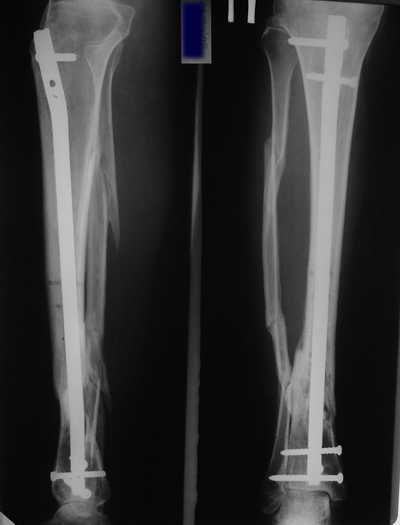

Женщина 46 лет, неудачно лечившаяся по поводу перелома голени в нижней 1\3 сначала в гипсе, поступила через 6 месяцев после остеосинтеза пластиной (рис 1). Имелась деформация в нижней 1\3 голени: варус, антекурвация, наружная ротация, два свища. Удалена пластина, дебридмент мягких тканей,

остеотомия м\б кости, аппарат Илизарова. По рентгенограммам в двух проекциях произведено планирование устранения смещений (рис 2 и 3), между вторым и третьим кольцом установлены 6 телескопических дистракторов Гесапода, данные введены в программу, и далее втечение 10 дней больная подкручивала телескопы согласно выданной компьютером инструкции. По завершению репозиции гексаподные телескопы обратно заменены на обычные штанги от аппарата Илизарова (рис 4 и 5). Еще через две недели забит гвоздь (рис 6, контроль

через 4 месяца).